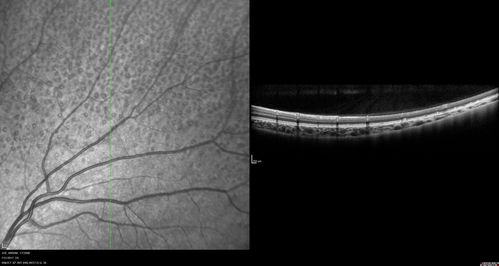

Fundus Albipunctatus

12 year old female with normal vision. She has 4 siblings all of whom have either white spots or spots on IR. Genetic testing by parents was deferred.